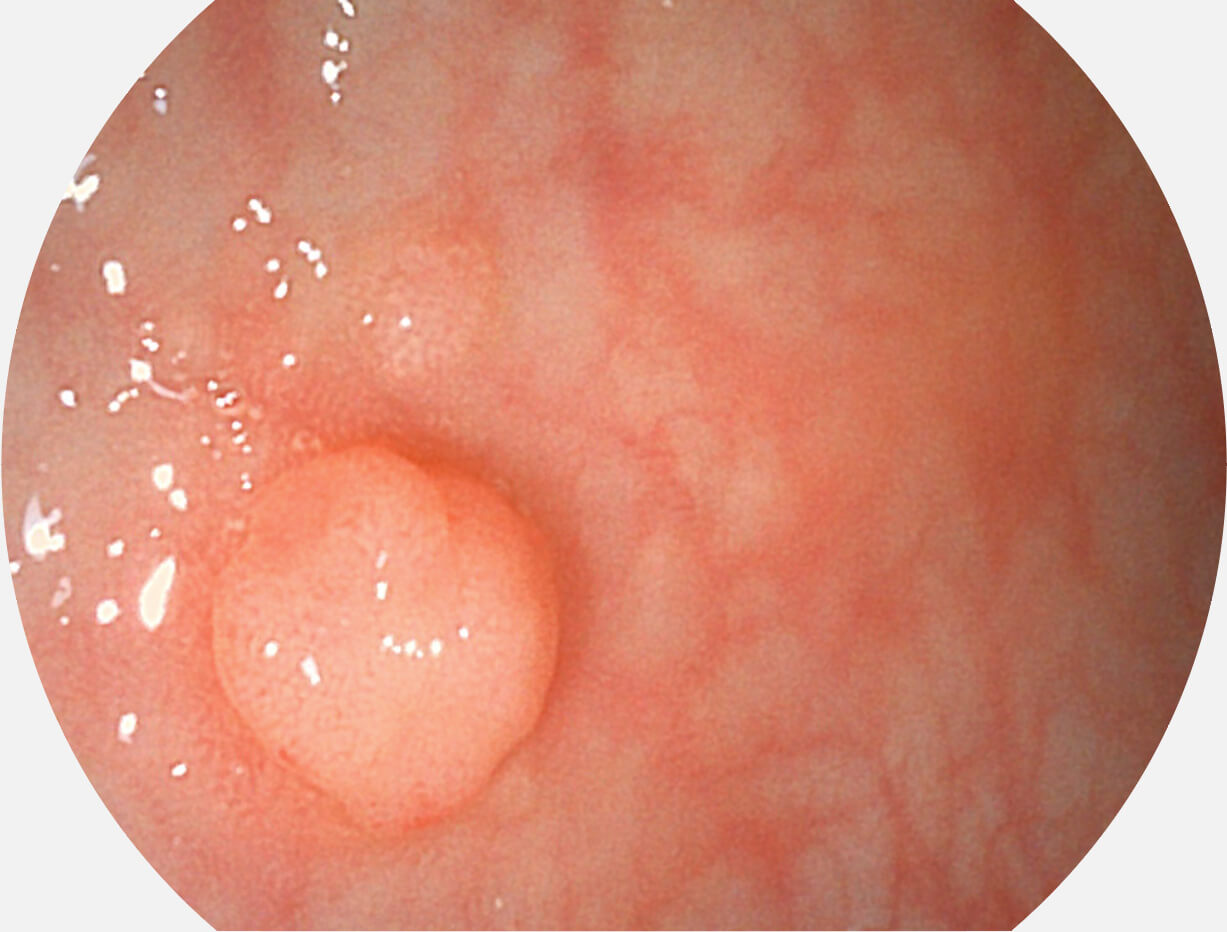

白光图像

SFI图像

图像具有高亮度、高黏膜血管颜色对比度的特点,且不改变粘液、食物残渣、粪便的基本颜色,可在中远景下进行观察,助力消化道早期疾病的诊断。

采用无损耗高清数字接口,视频输出分辨率≥1920×1080,图像清晰、细腻。